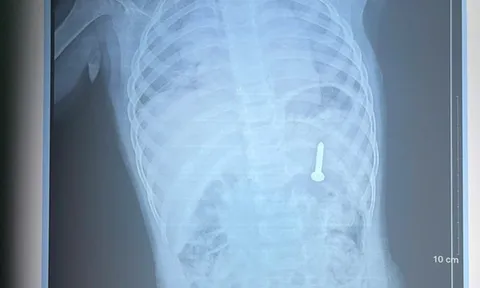

Tình trạng H. ho nặng hơn mới được đưa đi khám. Kết quả chụp cắt lớp vi tính tại bệnh viện địa phương phát hiện dị vật ở phế quản phải của bệnh nhân, sau đó trẻ được chuyển lên Bệnh viện Nhi Trung ương.

Tại Trung tâm Hô hấp, bệnh nhi được chỉ định nội soi phế quản để gắp dị vật. Quá trình can thiệp gặp nhiều khó khăn do dị vật đã tồn tại lâu ngày, bị bao bọc bởi tổ chức viêm và mô hạt. Các bác sĩ phải phối hợp nội soi ống cứng với laser để cắt bỏ tổ chức xung quanh và lấy ra dị vật là hạt hồng xiêm kích thước khoảng 1×3cm.